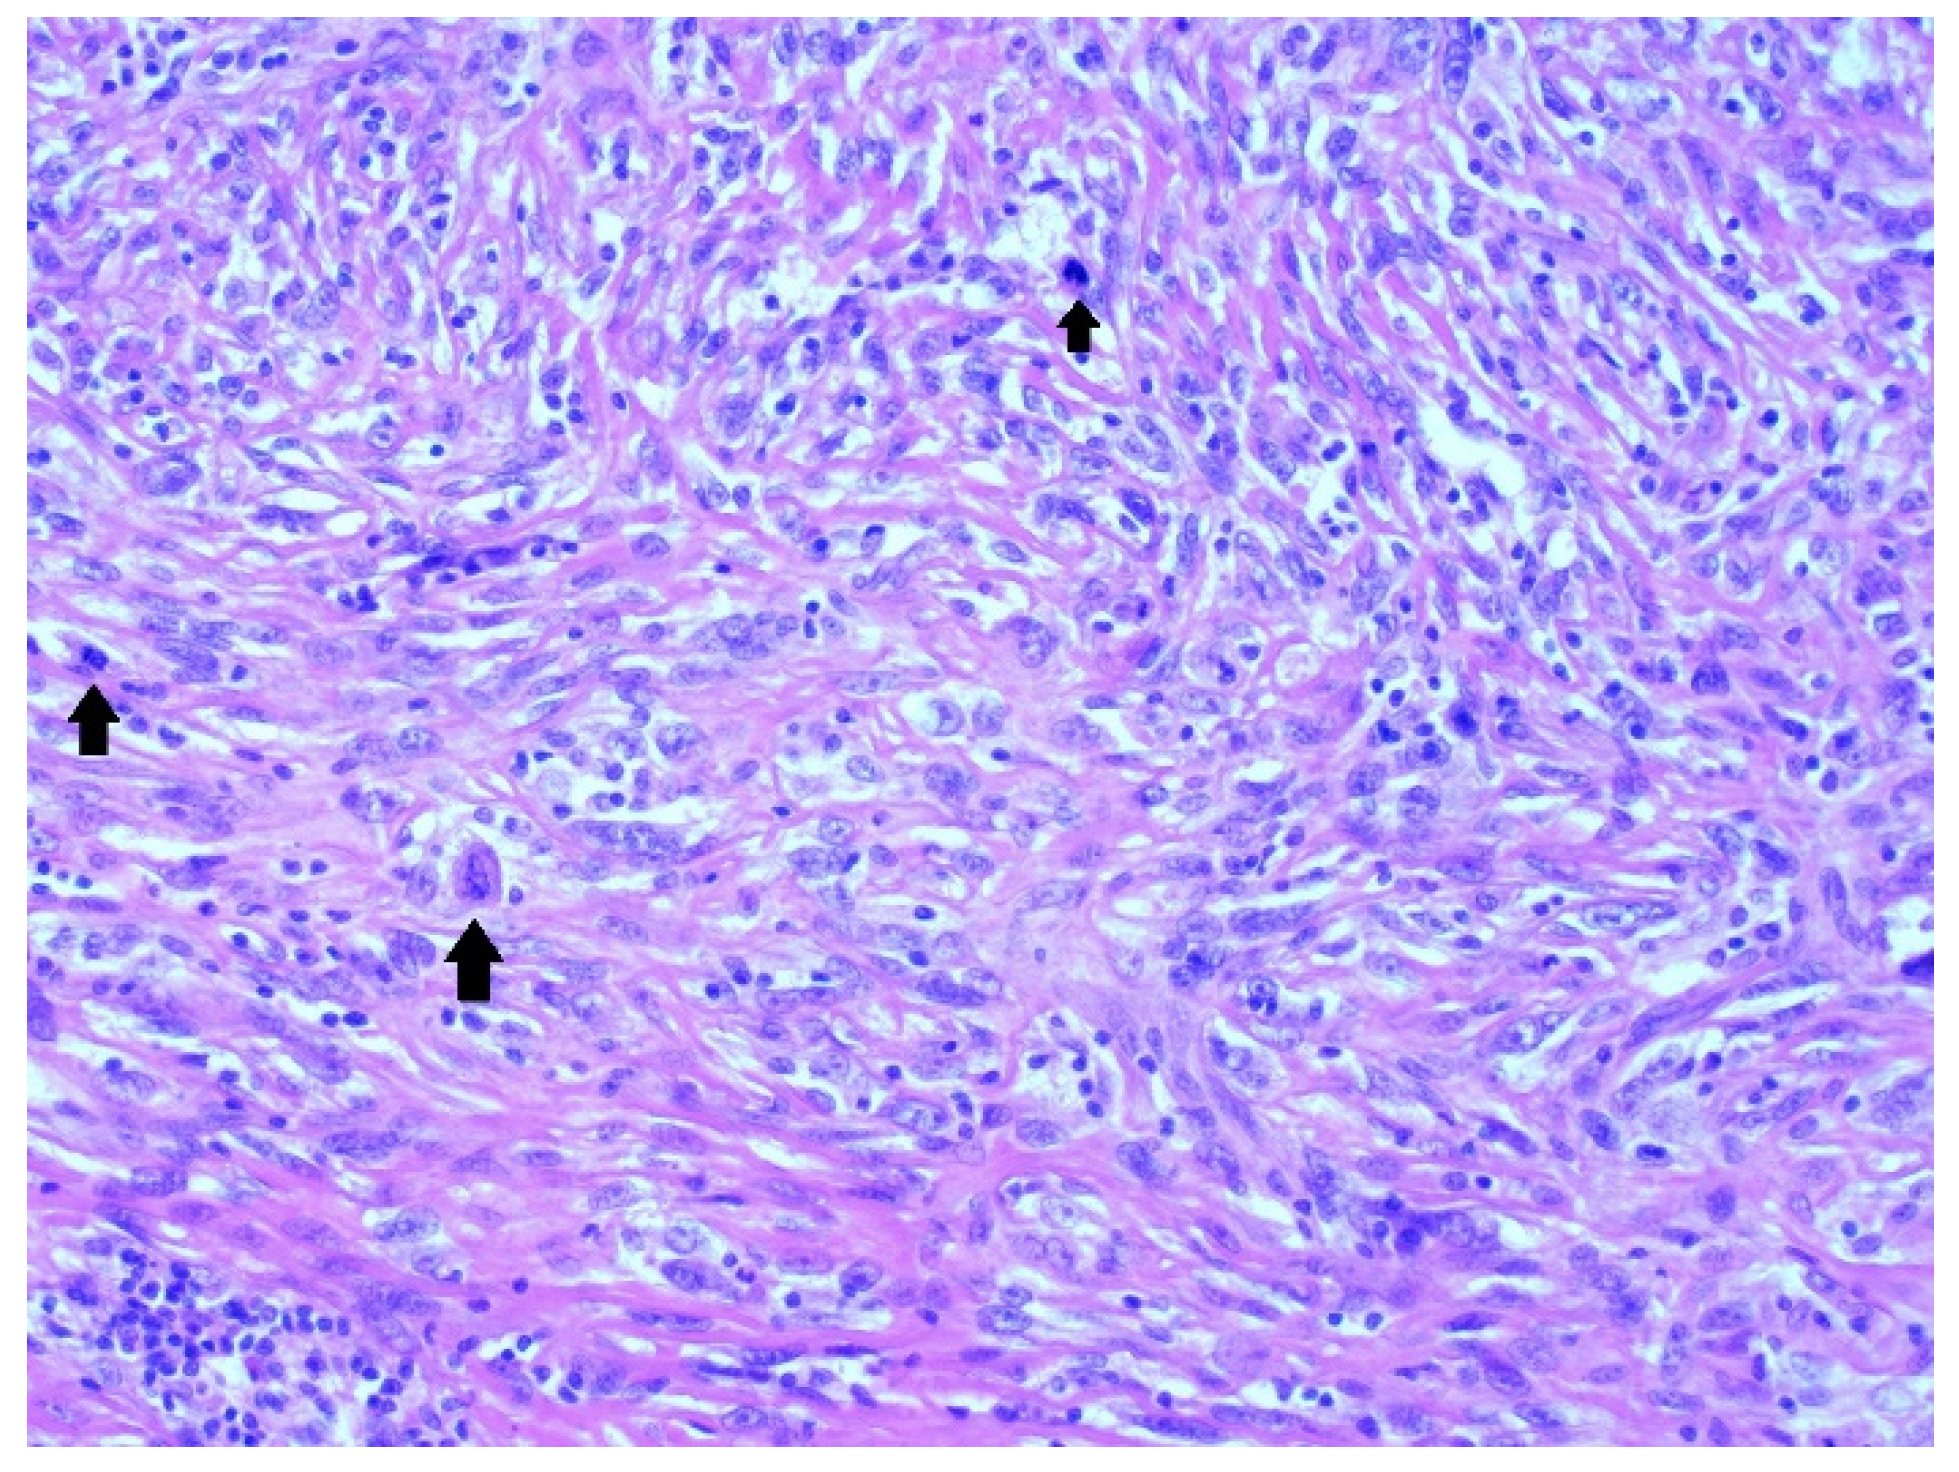

- Histopathology: complete investigation and extensive immunohistochemistry tests are necessary.